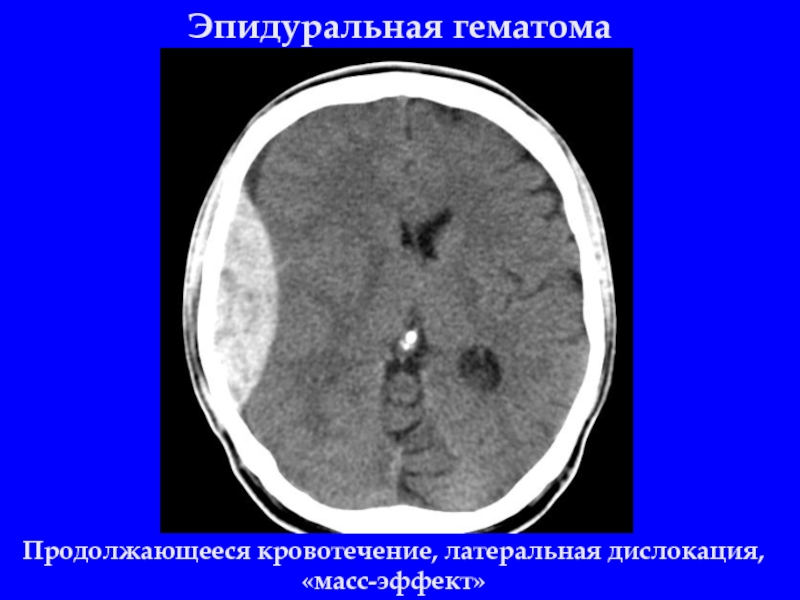

Слайд 9Эпидуральная гематома

Продолжающееся кровотечение, латеральная дислокация, «масс-эффект»